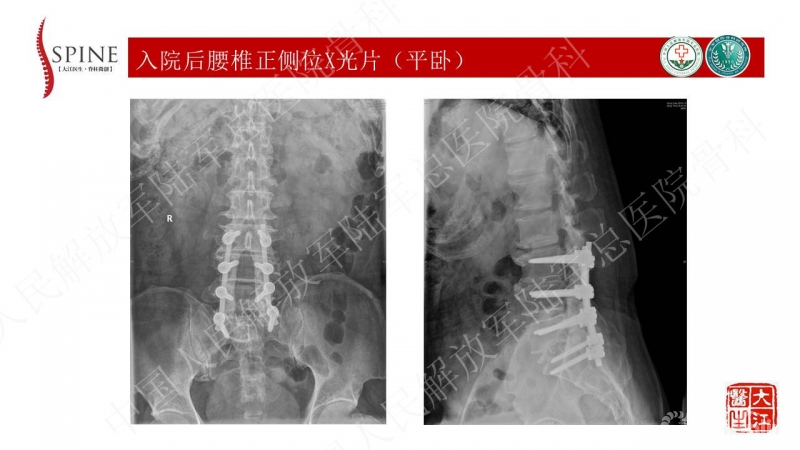

2013年曾因“腰椎管狭窄症”于外院行“腰椎减压、椎间植骨融合术”,术后大部分症状缓解,遗留部分右下肢麻木,效果满意

患者主诉为腰痛伴下肢疼痛,腰痛为主,翻身活动、下地时疼痛加重。体格检查也为下腰段的叩压痛,影像可见腰5-骶1断棒。断棒的原因都是力学应力相关的原因,而患者SVA(矢状位垂直轴)不大,全身平衡状态尚可。结合CT表现,应怀疑腰5-骶1节段未融合。

本病例的焦点在患者腰痛的原因,患者明确其腰痛非慢性腰痛,伤后出现。结合病史、体格检查、断棒的表现,主要考虑下腰段的原因。要考虑两个原因,一是腰5-骶1的未融合,断棒后不稳,局部应力集中。二是断棒后局部异常活动,带动瘢痕牵拉硬膜囊及神经根的向背侧牵拉,这种异常活动在残留小关节的抵挡下会引起严重卡压,而出现下肢的疼痛、甚至神经功能损害等。患者行原术区内固定取出,腰5-骶1内固定术,术后取得良好效果,证实患者本次疼痛病因为腰5-骶1节段断棒后应力集中、异常活动。

患者疼痛为伤后出现,不是根性痛表现,而是机械性疼痛,活动及下地时明确。上位节段已融合,考虑到长节段固定后腰5-骶1节段由于杠杆原理出现内固定失败的风险大,术中取出原内固定后,仅行腰5-骶1短节段固定,取得了良好的临床效果。美中不足的是,因椎管内瘢痕粘连重,未重新加强融合,之后需严密随访。